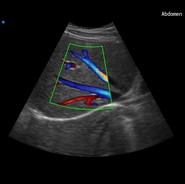

• Disponible opciones de Doppler Pulsado y Color Doppler

SONOLIFE-8800

Opción de Mapeo de Flujo a Color (Color Flow Mapping) :